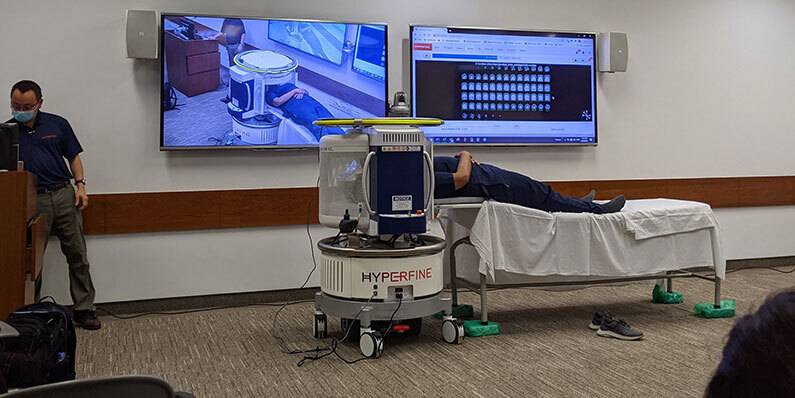

Ученые случайно открыли, что алмазная пыль светится при МРТ-исследовании. Это может стать безопасной альтернативой контрастному препарату на основе гадолиния. Сейчас при МРТ используют гадолиний, который накапливается в организме и может вызывать побочные эффекты. ferra.ru »